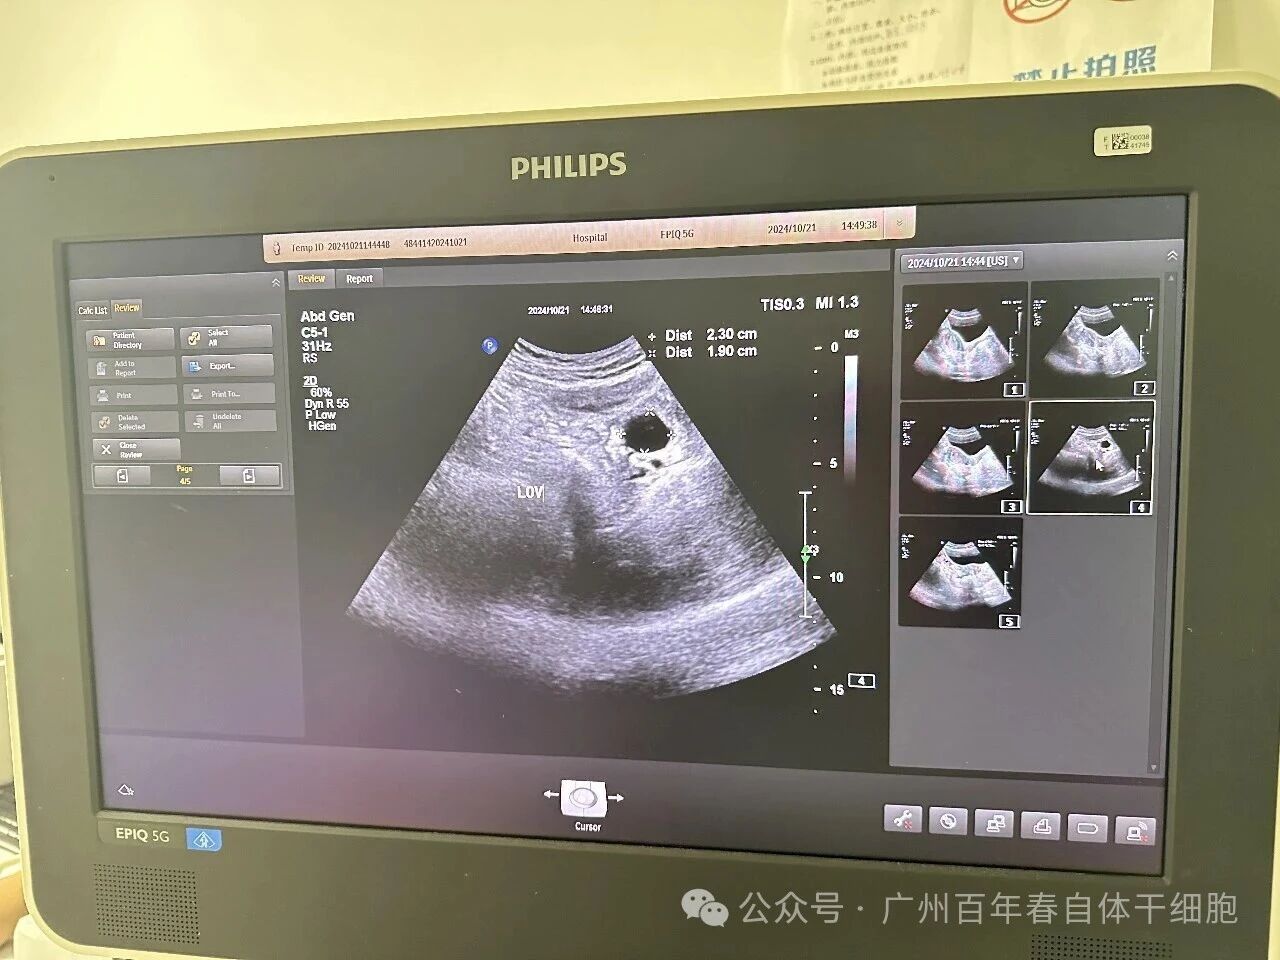

△保健前后B超对比

保健后两次监测B超结果都可见成熟卵泡及优势卵泡,卵巢体积增大,窦卵泡计数增多,雌二醇及AMH值逐渐上升。多次保健后更令人振奋的是,杨女士在停药后仍保持规律月经周期,且自然受孕成功,最终诞下健康婴儿。